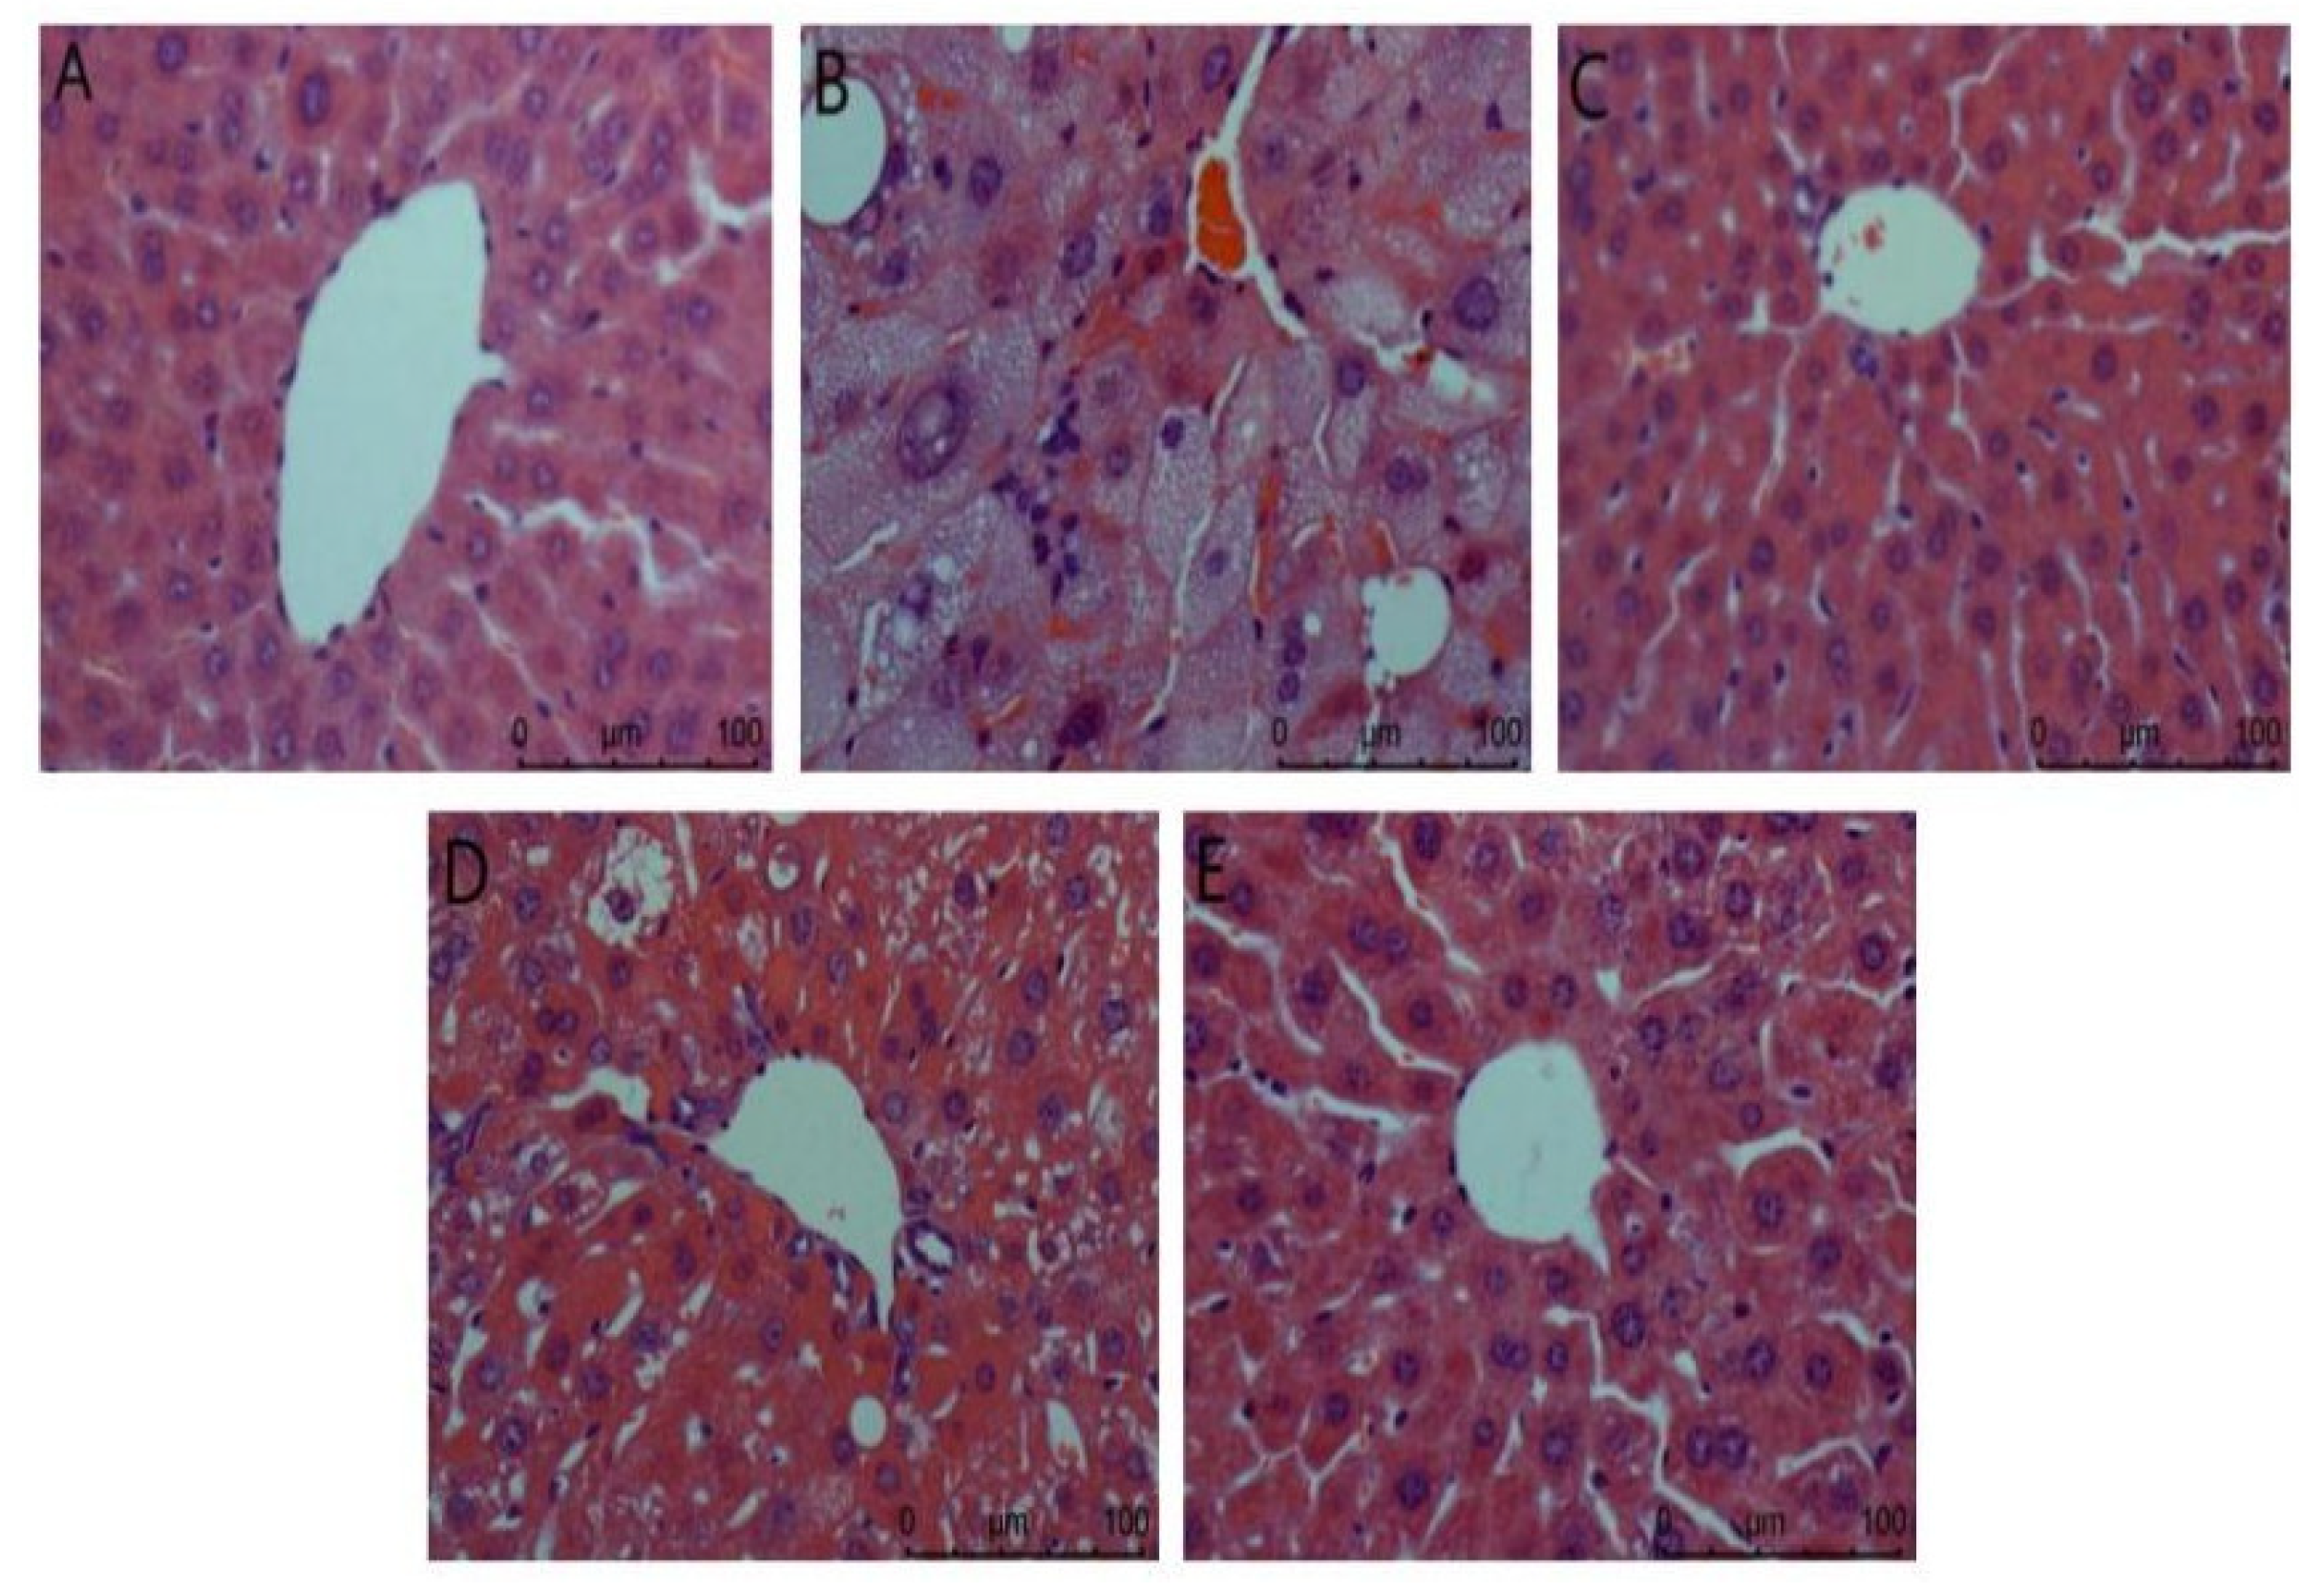

3.4.2. Effects of ACP on Organs of DM II Mice

- (1)

- Liver